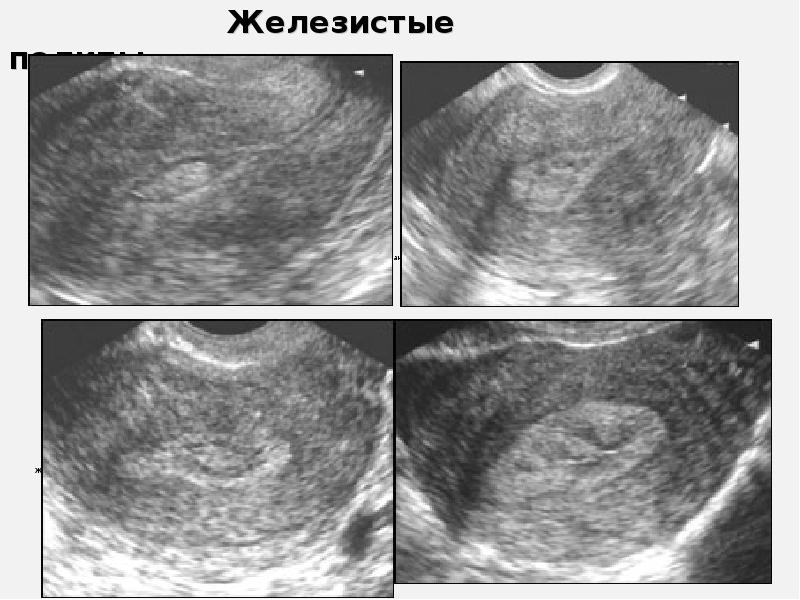

Медицинская диагностика: Гиперплазия эндометрия на УЗИ